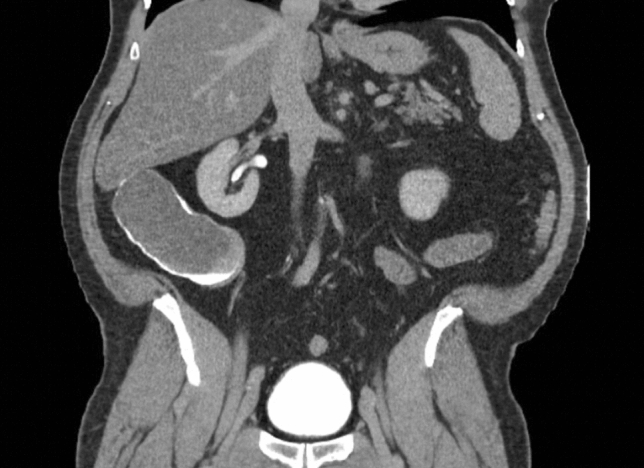

P041